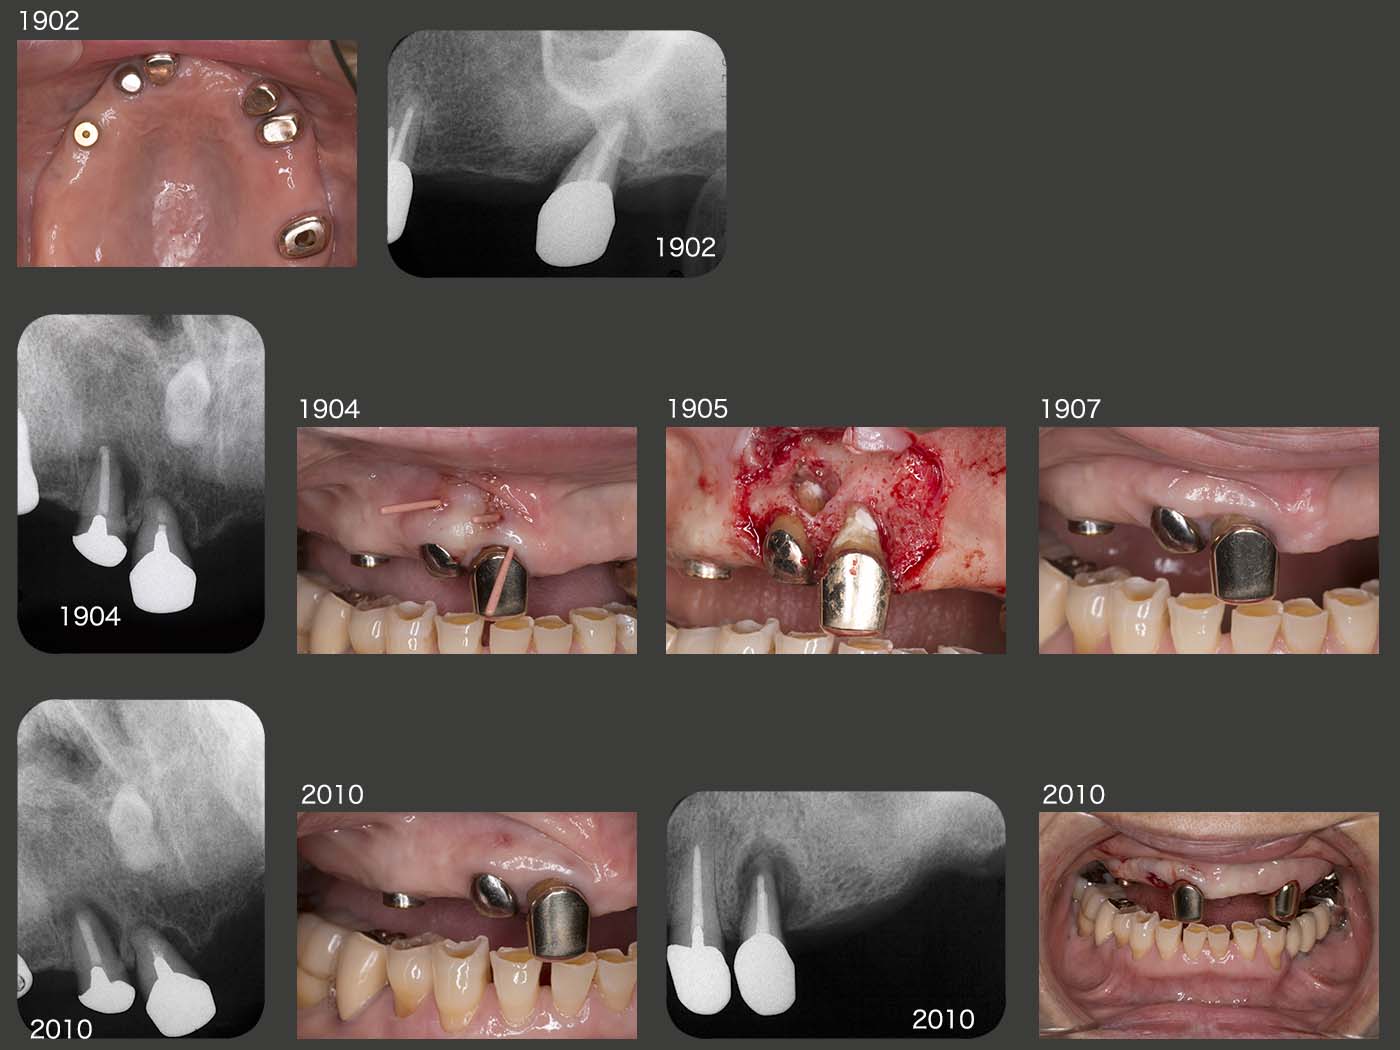

その後の経過は,右側が咀嚼側になったためか,まず右上5が2013年4月に歯根破折した.続いて15年1月,右上3に歯根破折が生じた.右上3という防波堤を失ったため,直ぐに右上1,2もドミノ倒し的に歯根破折が生じると考えた.それを阻止する目的で15年9月,右上4部にインプラントを1本植立した.インプラントと骨が結合する待機中に,今度は右上2にフィステルが生じた.また歯根破折と考えたが,歯周ポケットが最大5mmであったことから,根尖病巣の再発あるいは歯根破折の両方が疑われた.根尖は大きく拡大していたため,通常の感染根管治療は無理と判断した.15年12月,この歯を抜歯してよく観察したところ,幸い破折線が認められなかったので,根尖病巣と診断し,通法にしたがって再植した.補綴装置は,歯になるべく側方力をかけたくなかったので根面板とした.

2019年2月に左上7を歯周病にて抜去した.4月,15年に再植した右上2および右上1にフィステルが出現したので,右上2については歯根端切除術,右上1については穿孔らしき部位をスーパーボンドにて閉鎖した.7月の時点では,フィステルは消失した.しかし,20年10月,右上2に再びフィステルが生じたため,今回はさすがに諦め抜去した.また左上4に歯根破折が生じ,抜去した.まだ支台歯が2本(右上1は危険な状態)とインプラントが1本あるので,義歯の安定は問題ない.しかし,総義歯に誘導するか,左側にもう1本インプラントを追加するかの判断をする時期は近い.(私は,総義歯で十分と思われるが,最終的には口蓋義歯床の違和感を患者さんがどの程度訴えてくるかによる.)